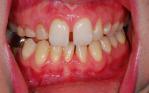

Orthodontic closure of the front gap and replacement of the loose baby teeth with some permanent implant crowns and bridgework.

Before